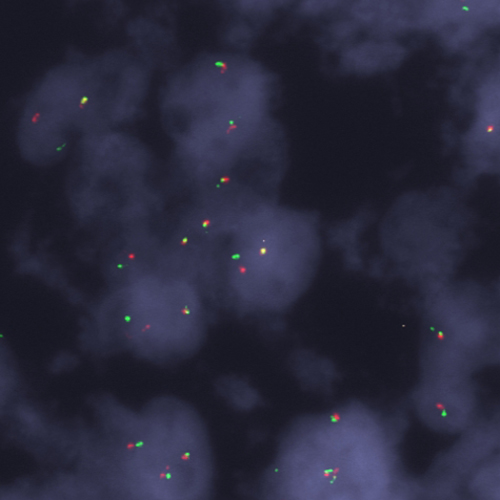

Liposarcoma stained using DDIT3 (12q13) Break – XL for BOND (KBI-XL015).

The DDIT3 (12q13) Break - XL for BOND FISH probe detects genomic translocations involving the DDIT3 gene. DDIT3 (12q13) Proximal - XL and DDIT3 (12q13) Distal - XL are optimized to detect genomic regions proximal and distal to break points in the DDIT3 gene region.

When combined, both probes are used to detect translocations involving the DDIT3 gene at 12q13.